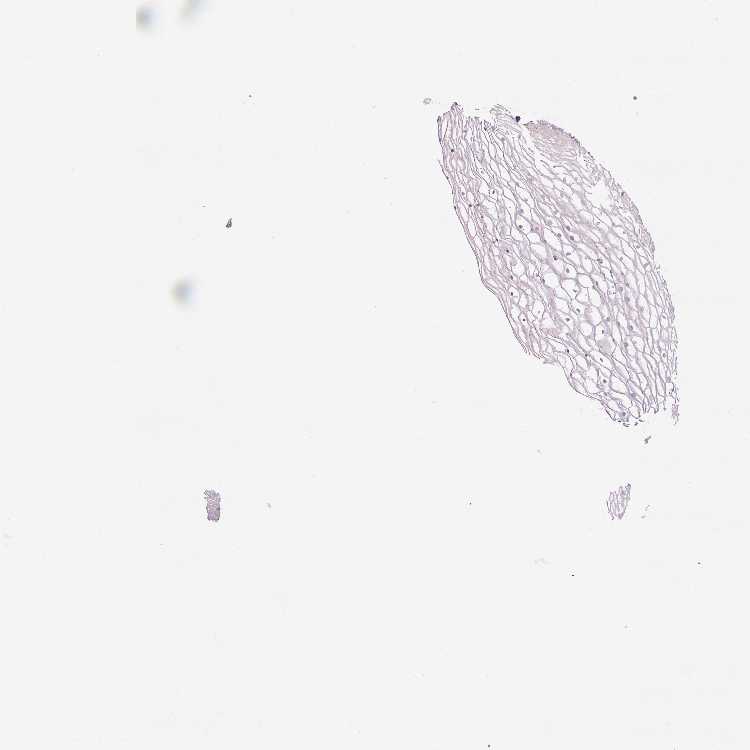

VAGINA - Antibody stainingi

Antibody staining in the annotated cell types in the current human tissue is reported as not detected, low, medium, or high, based on conventional immunohistochemistry profiling in selected tissues. This score is based on the combination of the staining intensity and fraction of stained cells.

Each image is clickable and will lead to virtual microscopy that enables deeper exploration of all samples and also displays staining intensity scores, fraction scores and subcellular localization as well as patient and tissue information for each sample.

Antibody HPA054844

Squamous epithelial cells Not detected